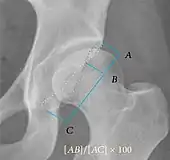

Center-edge angle of Wiberg | ![]() |

The superior-lateral coverage of the femoral head. | |

Crossing ratio | ![]() |

Percentage of acetabular walls crossing. Normal acetabulum is oriented in anteversion. Its value ranges from 15 to 20° in the equatorial plane of the acetabulum and decreases gradually towards the acetabular roof, where normal values range from 0 to 5°. Retroversion of the upper part of the acetabulum has been related with pincer type impingement. In radiography the presence of a "crossover sign" is produced when the posterior wall of the acetabulum crosses the anterior wall before reaching the acetabular roof. It is a sign of acetabular retroversion and it has been linked with overcoverage and pincer impingement. Nevertheless, this sign has been described in 6% of the normal population. Therefore, more important than its presence is the percentage of crossing. | <20%

|